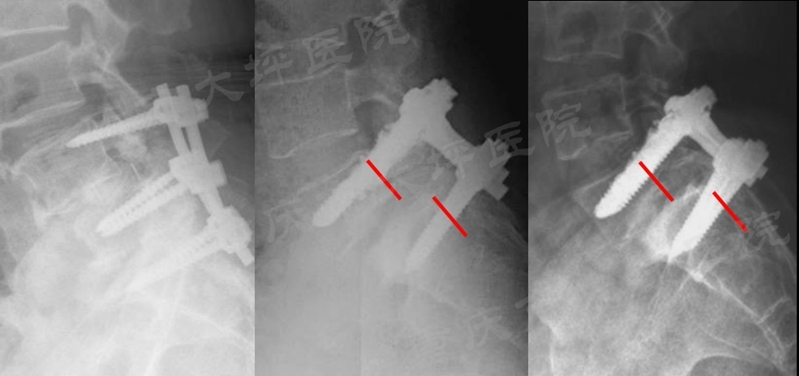

腰椎滑脱症是一种上位椎体相对于下位椎体向前滑移,以腰腿痛、间歇性跛行为主要症状的常见退变性脊柱疾病,成年人发病率约为6%。对于保守治疗无效的患者,采用后路椎弓根螺钉内固定技术复位滑移椎体、恢复腰椎序列、坚强固定达到骨融合是主要的治疗方式。然而,老年骨质疏松人群由于骨质疏松极大的降低了椎弓根螺钉的稳定性,极易发生内固定失败(图1)。

图1 腰椎滑脱内固定失败病例